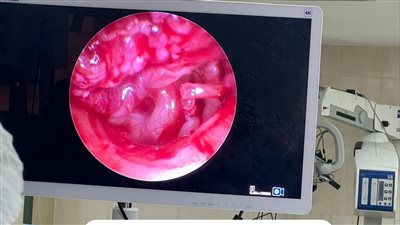

فريق طبي بمستشفي سوهاج الجامعي ينجح في اجراء عمليه رقع ورأب قاع الجمجمه

منذ سنتين